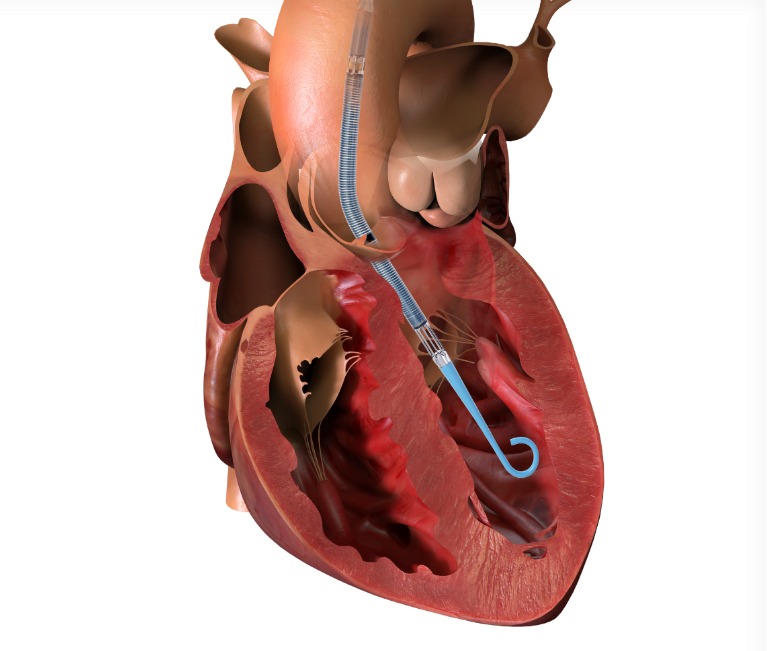

Enter the Impella – a tiny mechanical pump (thinner than a pencil!) inserted through the leg that travels to the heart. Think of it as a backup generator that keeps your house running while electricians fix the main power system.